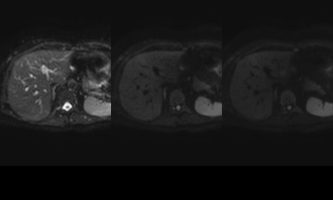

El estudio se complemento con resonancia magnética, donde se demostró la presencia de múltiples imágenes focales hepáticas confluentes con disminución de la señal en secuencias fuera de fase, no mostrando alteración de la señal en secuencias potenciadas en T2, sin signos de restricción al pulso difusión ni refuerzos anómalos luego de la administración de contraste endovenoso, estos hallazgos confirman la sospecha de esteatosis focal multinodular (fig. 5, 6 y 7).

En estos casos se recomienda realizar RM para confirmar la presencia de grasa en las “lesiones” identificadas y descartar otras etiologías, demostrando disminución de la señal en secuencias fuera de fase, sin alteración del pulso difusión (fig. 12 y 13).